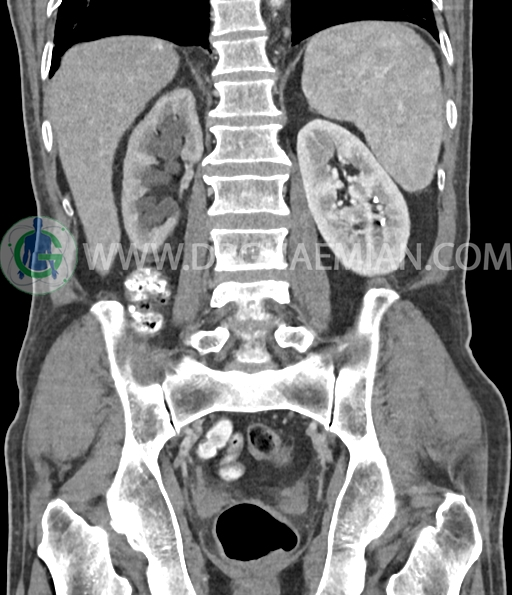

در سی تی اسکن اسپیرال شکم و لگن با و بدون کنتراست خوراکی و وریدی (مولتی دیدکتور 16 با مقاطع ظریف و بازسازی های ساژیتال و کرونال) :

ضایعه ای در کیسه صفرا، مجاری صفراوی، طحال، کلیه چپ ، پانکراس و آدرنالها مشهود نیست مایع آزاد در حفره شکم و لگن رویت نمی شود.

کیست کورتیکال به قطر 15mm در پل تحتانی کلیه چپ دیده می شود.

پروستات با دیامتر عرضی 60mmبزرگ تر از نرمال، همراه با bulging لوب مدین به کف مثانه رویت شد.

افزایش ضخامت جداری مثانه مشهود است.

افزایش ضخامت جداری و نامنظمی و لوبولاسیون همراه باenhancement مطرح کننده انفیلتراسیون و ضایعات تومورال در سمت راست ناحیه ترایگون و دیواره لترال راست مثانه دیده می شود که باعث اتساع حالب راست و هیدرونفروز moderate در کلیه راست شده است . این یافته های می توانند مطرح کننده TCC باشند .fat stranding در اطراف مثانه مشهود است. بیرون زدگی توده مانند به قطر 18mm در سمت راست ناحیه ترایگون دیده می شود که می تواند مطرح کننده گسترش اکسترا وزیکولر تومور باشد . لنفادنوپاتی با SAD=10mm درlevel ایلیاک داخلی چپ رویت شد . لنف نود دیگر با SAD= 5mm در همین ناحیه مشهود است. با توجه به این یافته ها stage احتمالی تومور T3، N1 or N2 می باشد .